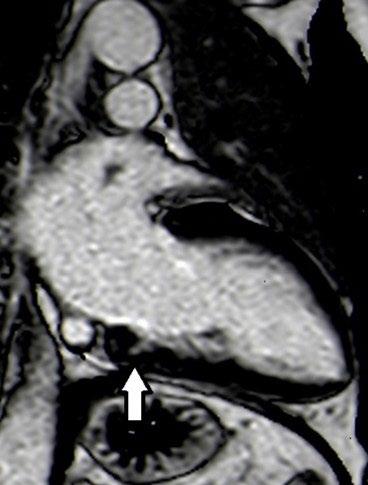

Create a flipbook